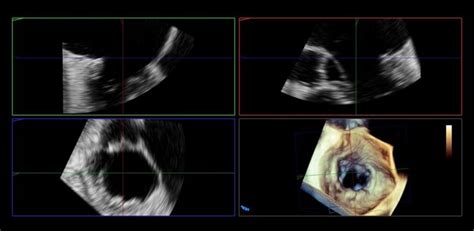

Oznámenie diagnózy zamlčaného potratu môže byť pre ženy veľmi traumatizujúce, najmä ak je podané necitlivo. Častokrát sa ženy dozvedia len strohú informáciu, že "tam nie je akcia". V ranom štádiu tehotenstva sa diagnóza stanovuje pomocou ultrazvukového vyšetrenia, ktoré posudzuje aktivitu srdcového svalu embrya. Vďaka pokročilej zobrazovacej technike, najmä transvaginálnemu vyšetreniu, sa limitácia tohto vyšetrenia posúva do nižších týždňov tehotnosti. Napriek tomu sa v nízkych týždňoch tehotnosti odporúča vyšetrenie zopakovať s odstupom aspoň 48 hodín, aby sa potvrdila neprítomnosť srdcovej akcie a zastavenie vývoja embrya.